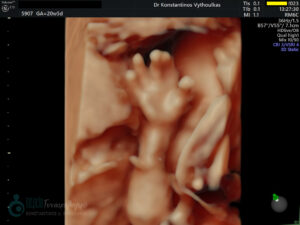

- Υπερηχογραφική εξέταση, η οποία συμβάλλει στη διαπίστωση της ενδομήτριας κύησης και αποκλεισμό της έκτοπης κύησης. Επιπλέον, μπορεί να διαπιστώσει εάν πρόκειται για μονήρη ή πολύδυμη κύηση, να ανιχνεύσει την εμβρυϊκή καρδιακή λειτουργία μετά τις 6 εβδομάδες και να προσδιορίσει υπερηχογραφικά την ηλικία κύησης, με βάση το κεφαλουραίο μήκος του εμβρύου μετά τις 8 εβδομάδες.